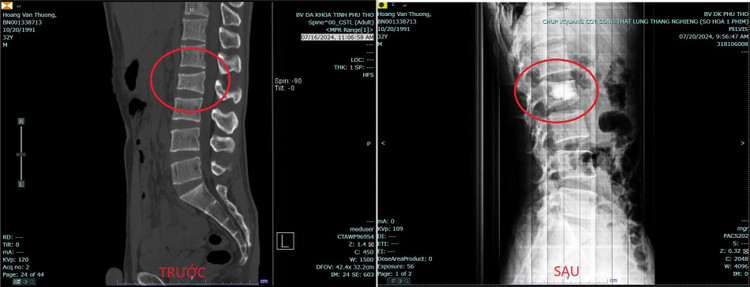

Người bệnh vẫn cảm thấy đau nhiều, ảnh hưởng rất lớn đến công việc và cuộc sống hàng ngày. Sau khi được thực hiện chụp chiếu và các cận lâm sàng cần thiết khác, kết quả cho thấy người bệnh có tình trạng lún thân đốt sống L2.

| Phim chụp của người bệnh trước và sau điều trị - Ảnh BVCC |

Ca phẫu thuật diễn ra nhanh chóng và thuận lợi. Chỉ sau một ngày người bệnh đã cảm thấy hết đau và có thể vận động bình thường, tình trạng sức khỏe trở lại như trước khi chưa bị ngã.